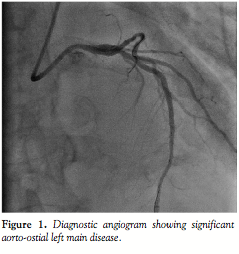

Case description. A 73-year-old man with stable angina and a significant

positive myocardial perfusion scan underwent elective coronary angiogram at our institution. There was significant ostial LM disease by angiography (Figure 1) and intravascular ultrasound imaging (IVUS). The best angiographic views were the right and left anterior oblique (RAO and LAO) with a cranial projection. A 6 Fr Judkins 4 guiding catheter was used and a workhorse wire inserted into the left anterior descending artery. Predilatation was done with a 3.0 mm balloon.